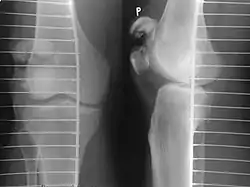

![]() | |

A fracture of the patella seen on a lateral view | |